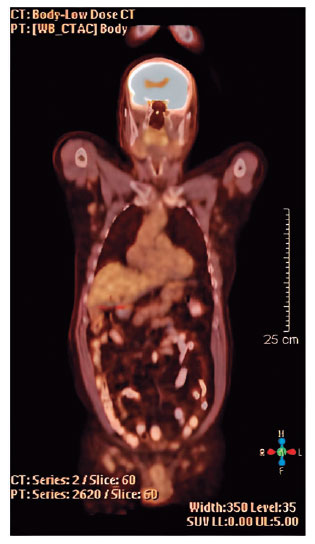

Histopathological and immunohistochemical findings revealed classical MCL (Figure 2). The patient was referred to the oncology department. Additional tests such as those for liver function, erythrocyte sedimentation rate, blood urea nitrogen level, creatinine level, β2 microglobulin level, lactate dehydrogenase level, leukocyte count, whole-body positron emission tomography (PET) (Figure 3), and bone marrow biopsy were performed.

The PET scan revealed multiple lymphadenopathies in the mediastinum, axillary fossa, and infra- and supra-diaphragmatic paraaortic areas. Bone marrow examination revealed involvement of the bone marrow. The patient was classified as having T4N3M1c disease according to the TNM staging system for ocular adnexal lymphoma (Table 1).